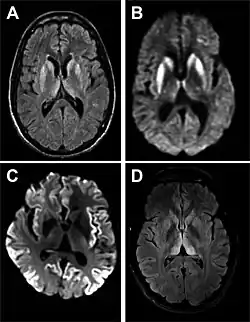

- MRI with diffusion weighted inversion (DWI) and fluid-attenuated inversion recovery (FLAIR) shows a high signal intensity in certain parts of the cortex (a cortical ribboning appearance), the basal ganglia, and the thalami.[42] The most common presenting patterns are simultaneous involvement of the cortex and striatum (60% of cases), cortical involvement without the striatum (30%), thalamus (21%), cerebellum (8%) and striatum without cortical involvement (7%). In populations with a rapidly progressive dementia (early in the disease process), MRI has a sensitivity of 91% and specificity of 97% for diagnosing CJD.[46] The MRI changes characteristic of CJD may also be seen in the immediate aftermath (hours after the event) of autoimmune encephalitis or focal seizures.[42]

Imaging of the brain may be performed during medical evaluation, both to rule out other causes and to obtain supportive evidence for diagnosis. Imaging findings are variable in their appearance and also variable in sensitivity and specificity.[49] While imaging plays a lesser role in diagnosis of CJD,[50] characteristic findings on brain MRI in some cases may precede onset of clinical manifestations.[51]

Brain MRI is the most useful imaging modality for changes related to CJD. Of the MRI sequences, diffuse-weighted imaging sequences are most sensitive.[52] Characteristic findings are as follows:

- Focal or diffuse diffusion-restriction involving the cerebral cortex or basal ganglia. The most characteristic and striking cortical abnormality has been called "cortical ribboning" or "cortical ribbon sign" due to hyperintensities resembling ribbons appearing in the cortex on MRI.[53] The involvement of the thalamus can be found in sCJD, is even stronger and constant in vCJD.[54]

- Varying degree of symmetric T2 hyperintense signal changes in the basal ganglia (i.e., caudate and putamen), and to a lesser extent globus pallidus and occipital cortex.[50]

| Signal hyperintensity in the caudate nucleus and putamen on diffusion-weighted and FLAIR MRI | Often present | Often absent |

| Pulvinar sign-bilateral high signal intensities on axial FLAIR MRI. Also, posterior thalamic involvement on sagittal T2 sequences | Not reported | Present in >75% of cases |